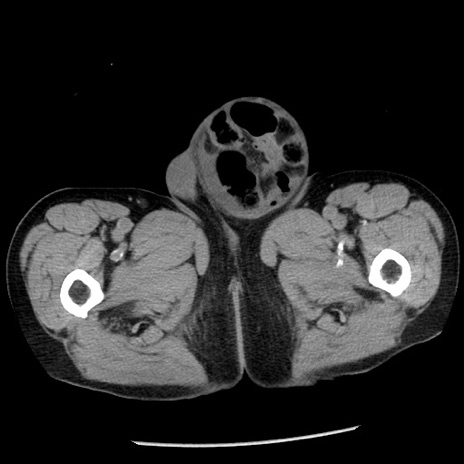

症例26(横断像)

【症例】80歳代男性

【主訴】嘔吐

【現病歴】昨晩2回嘔吐あり、今朝になっても嘔吐あり。来院。

【既往歴】胃潰瘍

【身体所見】意識清明、BT 37.6℃、BP 166/95mmHg、HR 100bpm、SpO2 97%、腹部:平坦・軟、腸蠕動音聴取良好、圧痛なし。

【データ】WBC 21900、CRP 1.46